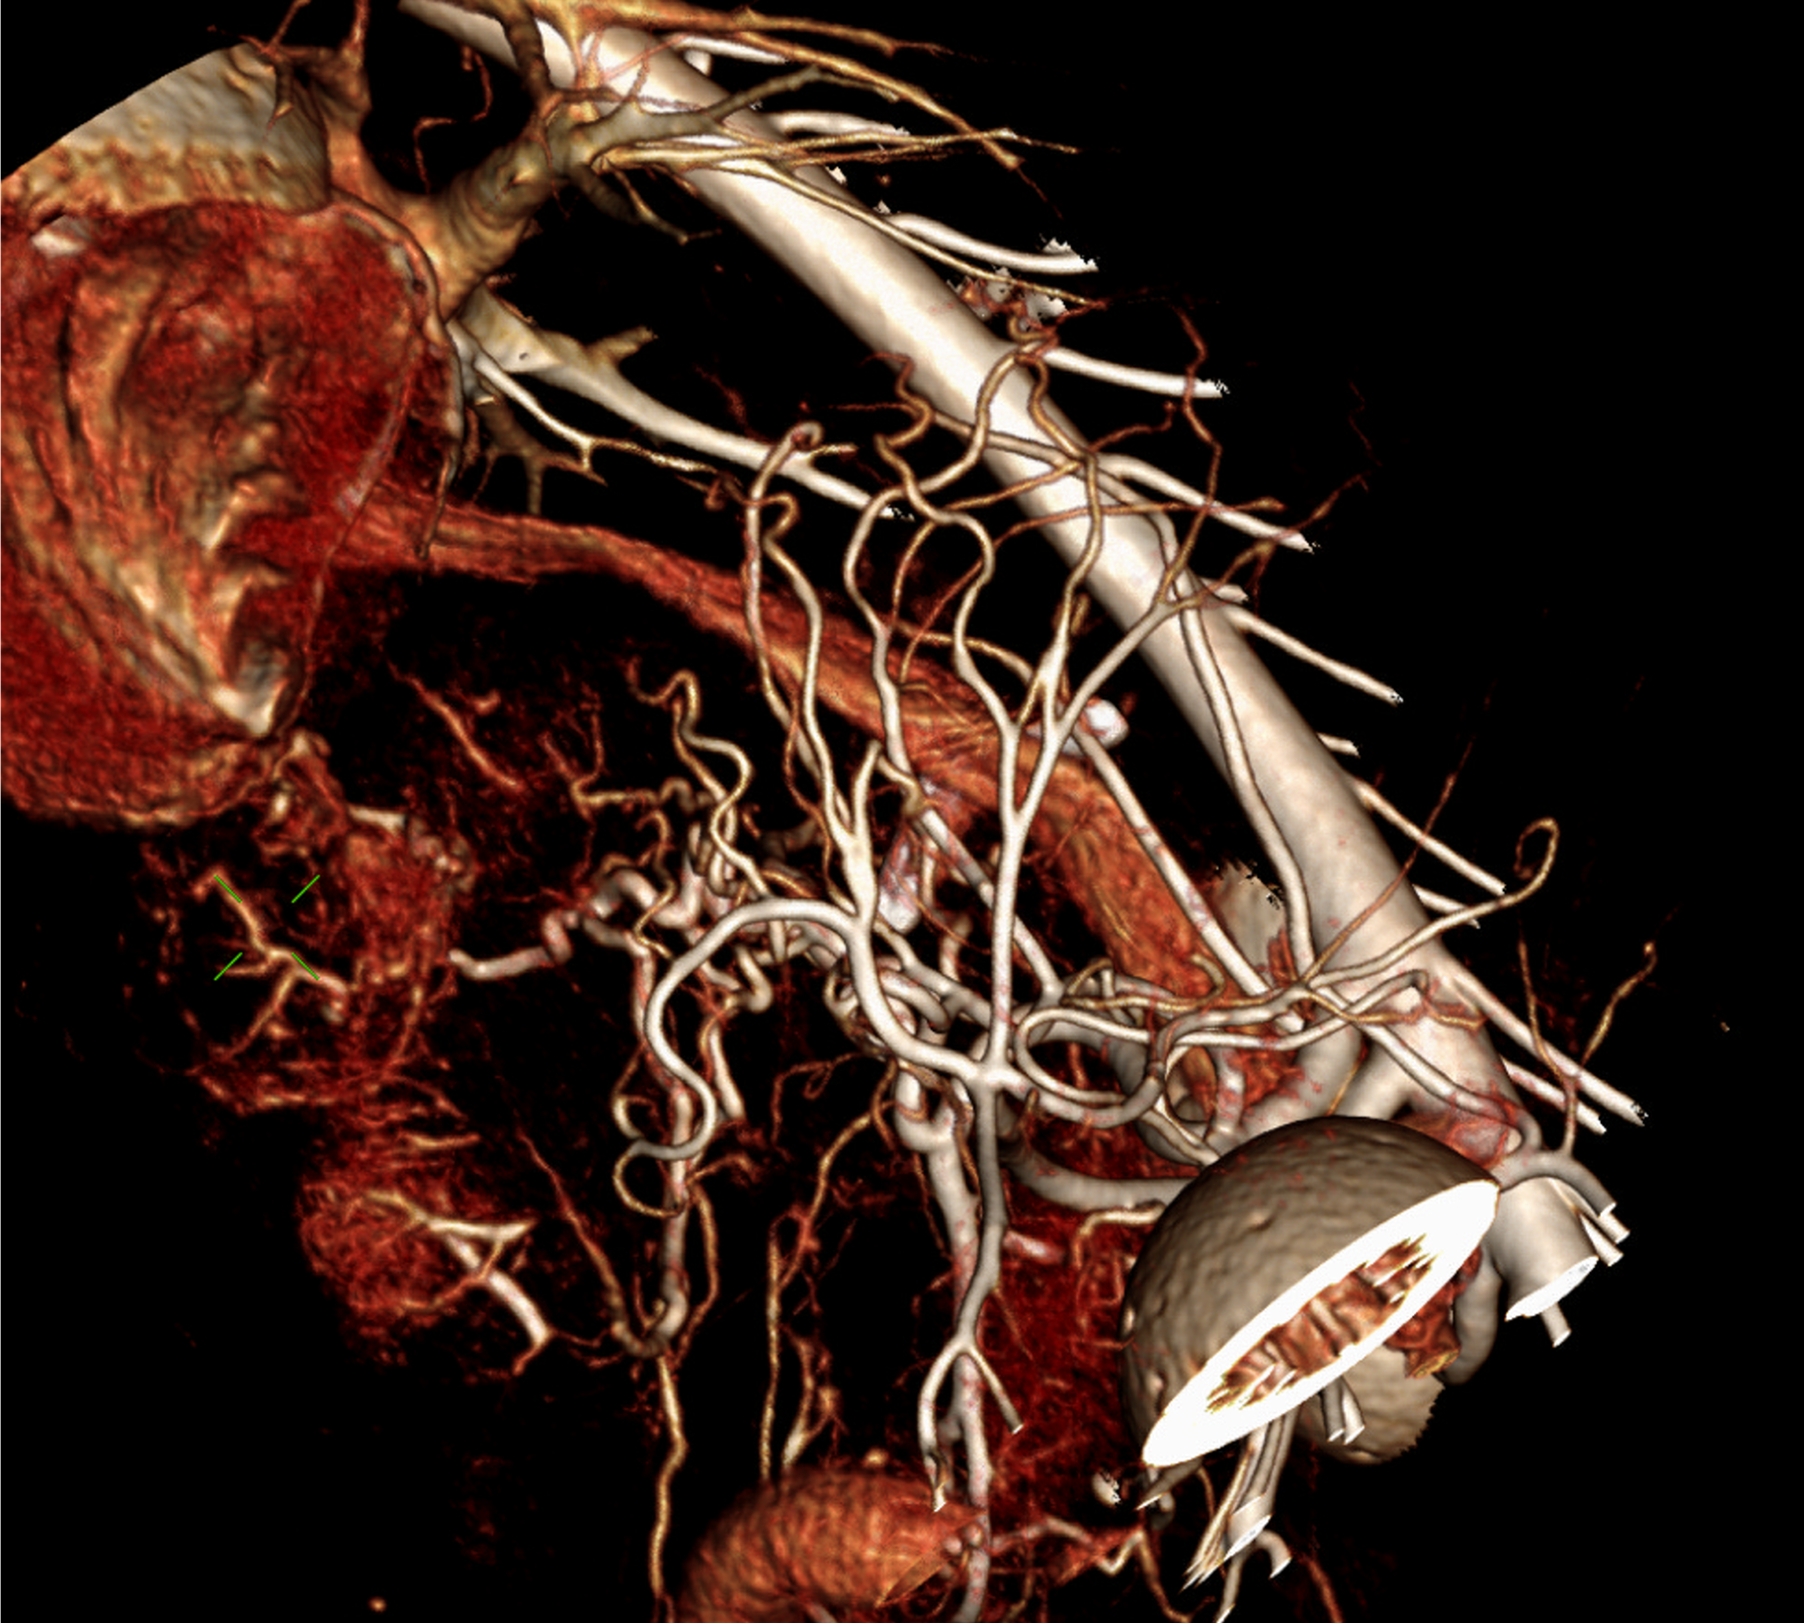

160ch CT

160 slice CT는 빠른 속도로 환자의 마취 시간을 줄이며(5분 이내) 정확한 진단에 도움을 줍니다. 또한 심장 등의 장기를 평가함에 있어 기존 64채널 CT에 비해

우수한 해상도의 영상을 획득 가능합니다.

160 slice CT는 국내 동물병원에서 최상급 촬영장비(Toshiba Acquilion Prime)에 해당하며 conventional CT 촬영 이외에도 추가적인 body perfusion,

dual energy 등도 가능합니다.

160채널 CT는 고화질 영상으로 숨어있는 비정상적인 문제점들을 찾아내어 진단 및 치료에 도움을 주고 있습니다.

3D 재구성을 통해 외과의에게 더욱 정확한 정보를 제공할 수 있어 수술의 위험성을 감소시킵니다.

3kg cardiac CT 3D recon

4kg abdominal aorta 3D recon